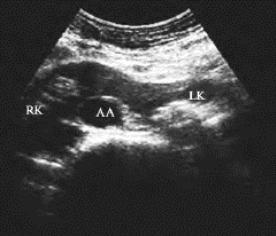

3.马蹄肾超声表现 中腹部腹主动脉与下腔静脉前方见椭圆形低回声区,回声强度与肾实质相似,其两侧与双肾下极相连(图29-13)。双肾下极均靠近中线,相距较近。

图29-13 马蹄肾声像图

腹主动脉前方见低回声区,回声强度与肾实质相似,其两侧与双肾下极相连